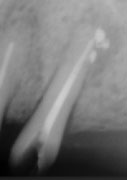

したがって、院長が大学生だった時に学んだ、ステンレススチールのファイル(根の中を掃除する道具)では根の湾曲に追従しないため、当院では全症例ニッケルチタンという柔軟な新しい素材で作られたファイル(従来のステンレススチールに比べ約5倍高価)で根の神経をとった穴を清掃しています(図3)。

図3